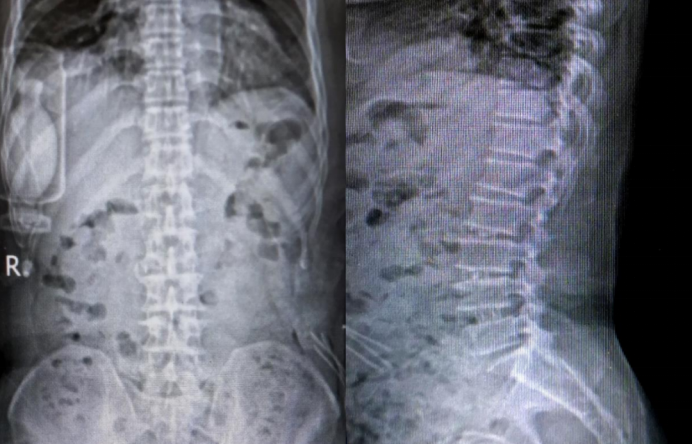

Preoperative Imaging